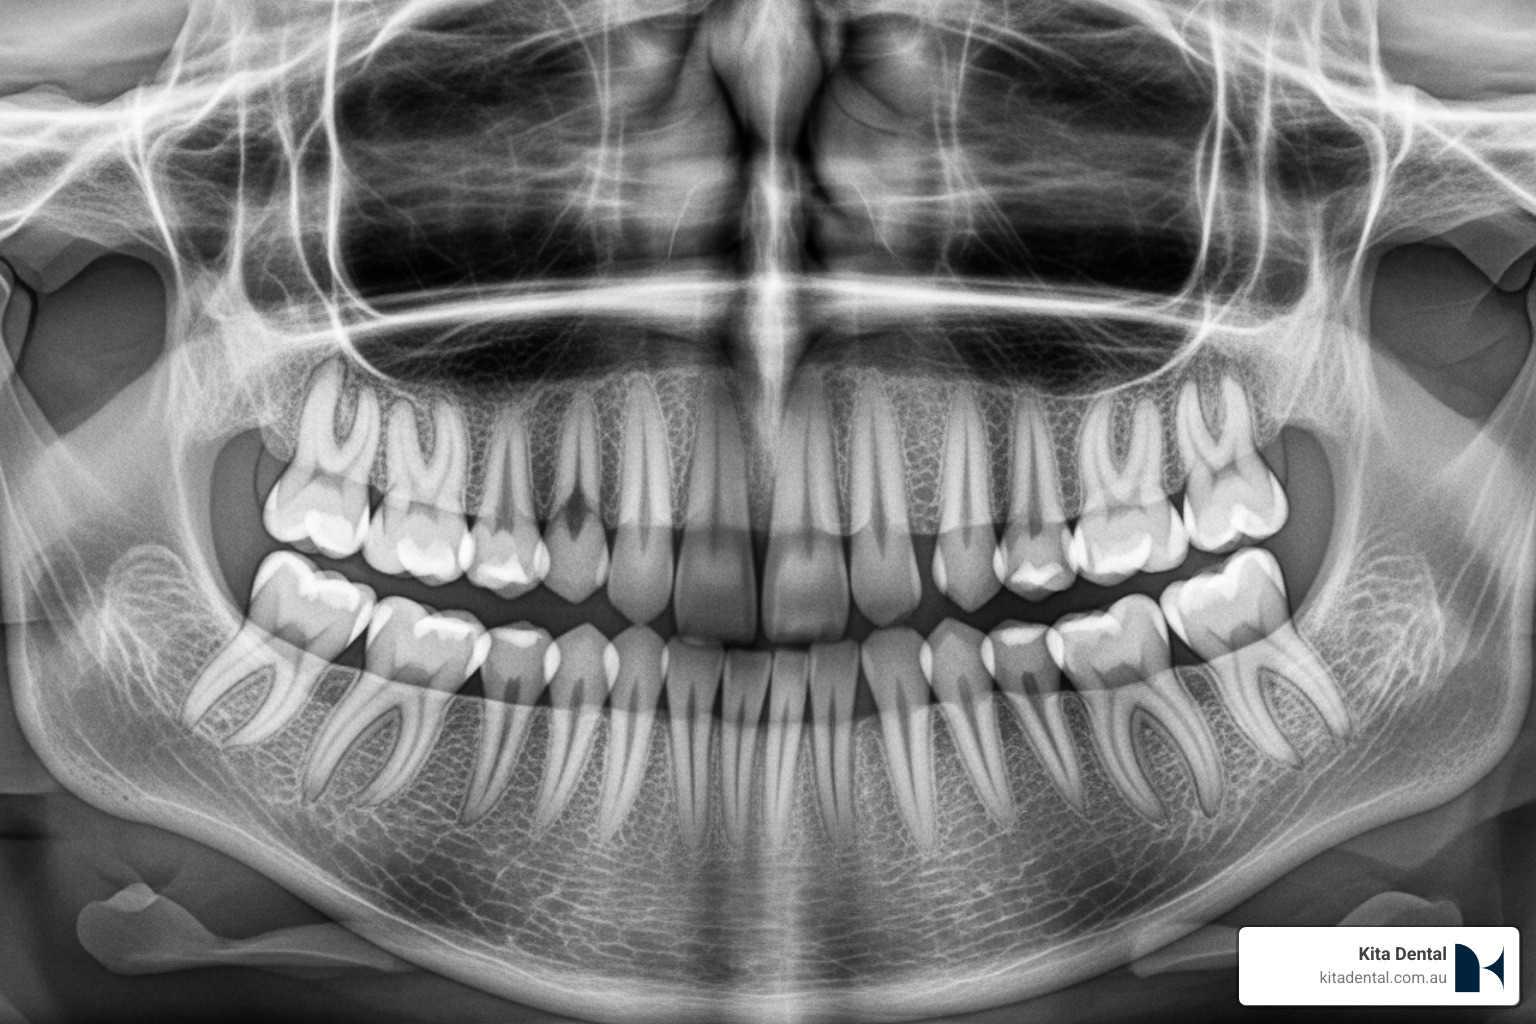

For patients considering full arch restoration, understanding your current bone health helps determine whether you’re a candidate for immediate implant placement or if you might benefit from bone grafting first. Advanced 3D imaging is used to assess your bone quality and develop the most appropriate treatment plan for your unique situation.

Your journey begins with a comprehensive consultation at a Mascot clinic. We use advanced 3D CBCT imaging to map your jawbone precisely, determining exactly where grafting is needed and which material will work best for your situation.

The key to success with any graft-less approach lies in thorough evaluation and expert planning. Using advanced 3D imaging, a dentist can determine exactly which technique will deliver the best results for your unique situation, ensuring your new smile is both beautiful and built to last.

Advanced 3D imaging is used to assess your bone quality, helping you and your dentist understand which approach offers the best combination of predictability, comfort, and timeline for your unique situation.